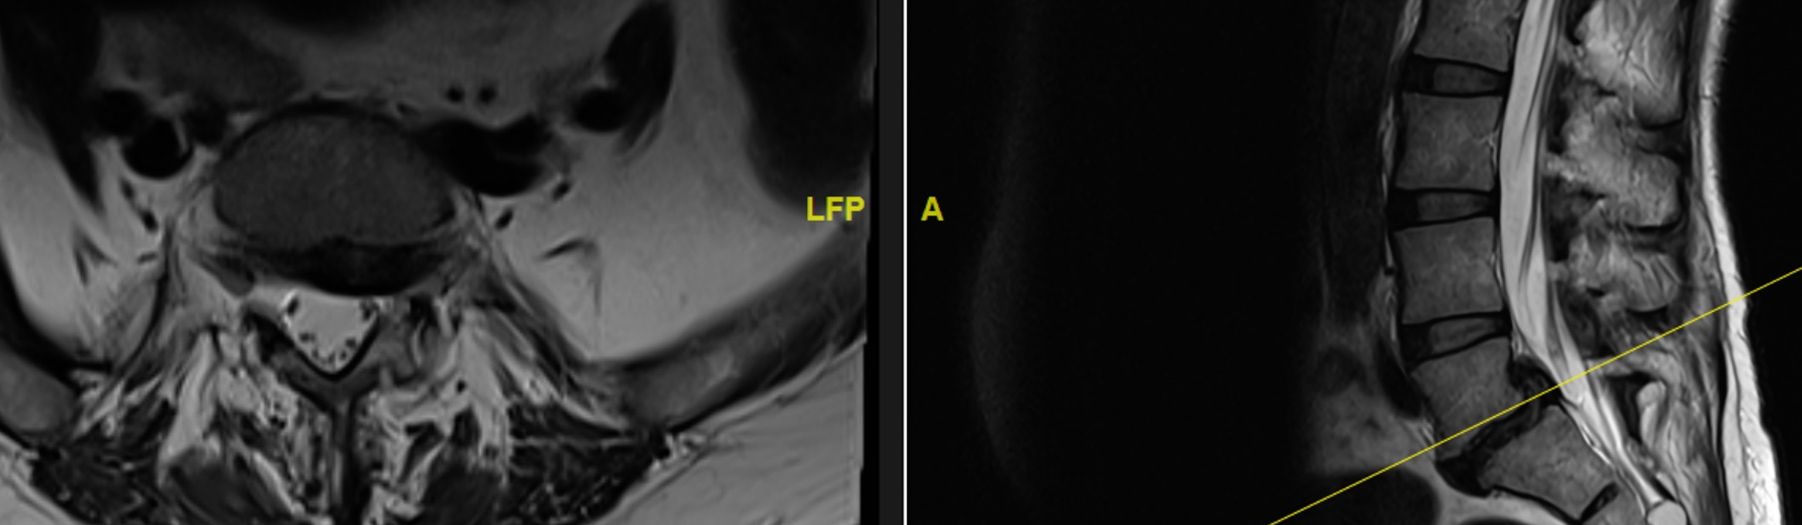

ALIF Approach and sequestrectomy